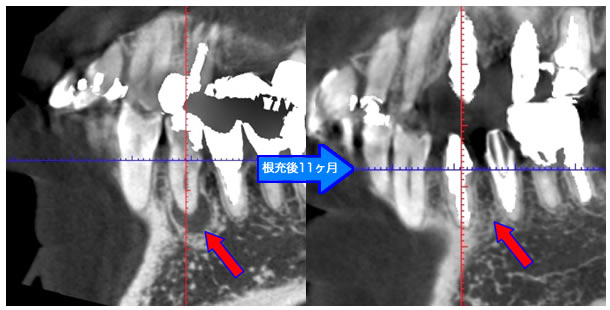

頬側骨壁の根尖部まで無くなっています。

MTA根充後11ヶ月で透過像が消失し、根尖部が正常化しました。

頬側骨の喪失が見られましたが17ヶ月で回復しました。

| 治療説明 | 左下第一小臼歯の頬側根尖部からの排膿、痛みはないそうです。X線画像では根尖部に透過像を認められます。 頬側の骨も失われており、歯髄が死んだことが原因と考えられます。修復物を除去後根管治療を行い、根管充填後、透過像は消失、頬側骨も再生されていました。 |